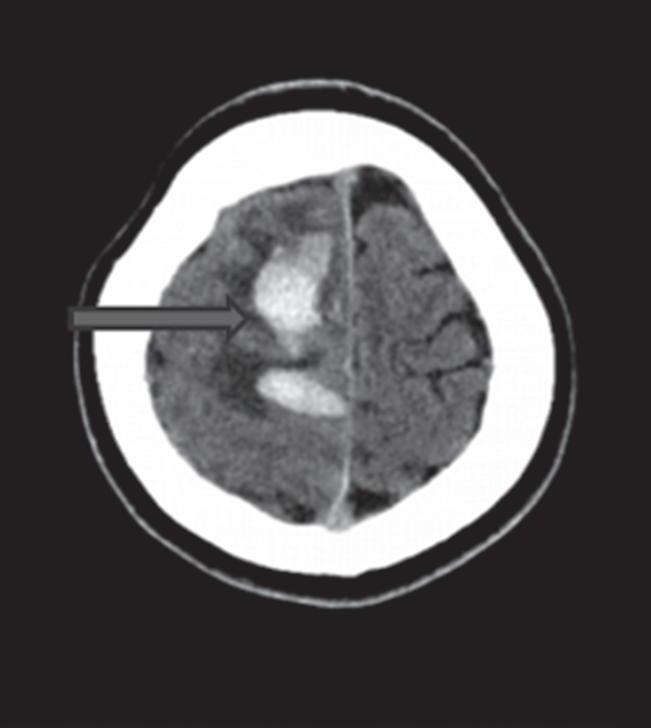

Com relação à apresentação clínica, as MAVs podem ser classificadas em dois grandes grupos: rotas e não rotas, como representado nas Figuras 1-5 a 1-7. As MAVs não rotas subdividem-se em dois subgrupos: sintomáticas e assintomáticas, sendo a crise convulsiva o sintoma mais comum nas MAVs não rotas; embora a importância das crises epilépticas seja muitas vezes negligenciada em favor da hemorragia intracraniana, que é o evento mais frequente e temido da história natural das MAVs. Em contrapartida, as crises epilépticas não devem ser deixadas em segundo plano porque podem ser debilitantes e comprometer a qualidade de vida do paciente.23,25

Outra classificação relacionada com a topografia divide as MAVs em: parenquimatosas, durais puras e mistas (durais e parenquimatosas). As parenquimatosas subdividem-se em: piais, subcorticais, paraventriculares (Fig. 1-10) e combinadas. Sendo que as piais, quando rompem, estão associadas mais frequentemente à hemorragia subaracnóidea e as paraventriculares associam-se ao hemoventrículo associado ou não à hidrocefalia obstrutiva.26